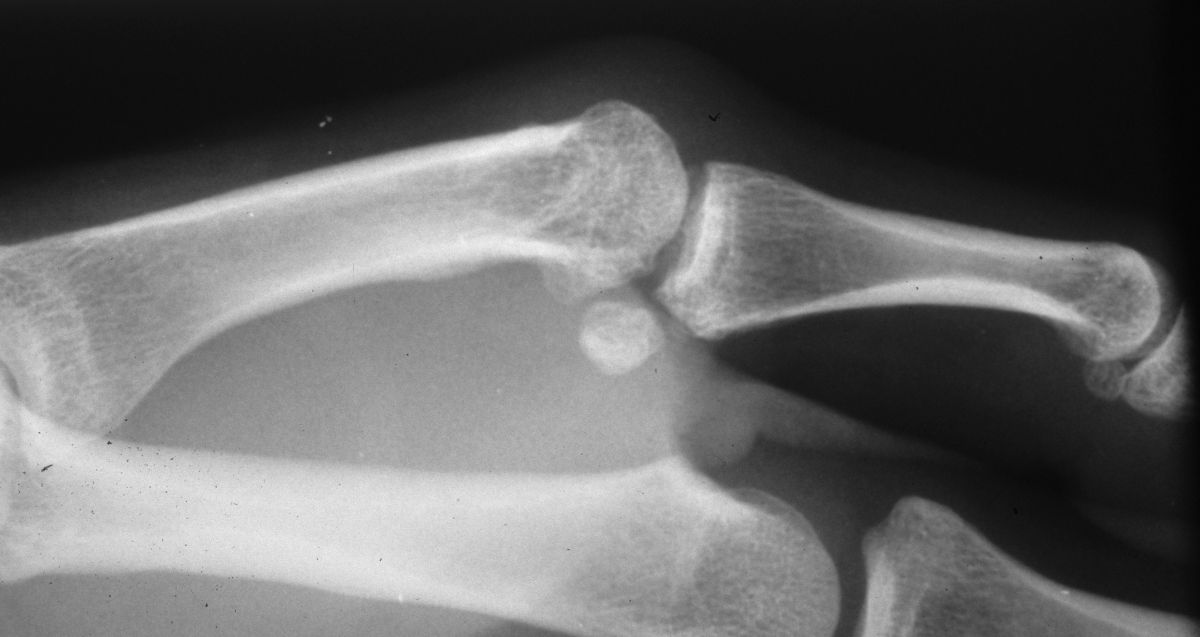

| This patient had chronic

pain and instability from an old radial collateral ligament rupture

followed by both metacarpophalangeal and sesamoid metacarpal arthritis |

| The Synthes mini fragment

system was used, with a lag screw across the fusion site and

sesamoid excision. |

| Although the patient healed

uneventfully, the screws seem excessively large for these bones. |